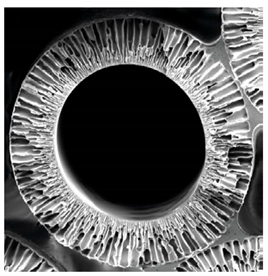

| Cellulose-Based (Cuprophan) | Synthetic (Polysulfone) |

![]() | ![]() |

| Natural polymer | Synthetic polymer |

| Homogeneous | Asymmetry |

| Hydrophilic (hydrogel) | Hydrophobic structure |

| Low hydraulic permeability | High hydraulic permeability |

| Low sieving properties | High sieving properties |

| Prevalent use in hemodialysis | Exclusively used for hemofiltration |